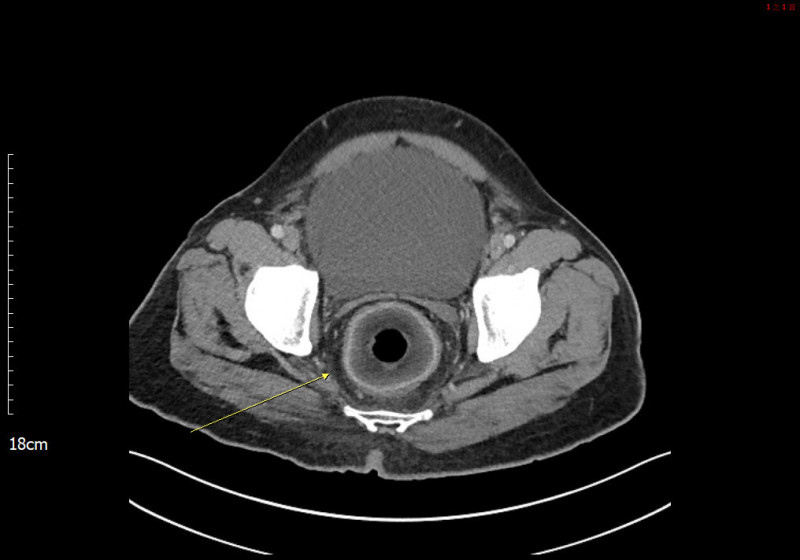

根據媒體《中時新聞網》、《ETtoday新聞雲》的報導,高雄一名50多歲的男子因為劇烈腹痛到義大醫院掛急診,稱自己已經肚子痛了2天,不僅便祕還小便上不出來。醫生細問後,男子坦承2天前曾塞東西進菊花,進一步安排電腦斷層掃描,醫生果然在他直腸發現一顆巨型圓狀物,因為壓迫到尿道才導致無法正常排泄。

由於男子膀胱約有2000c.c.的尿液無法排出,膀胱腫得像顆橄欖球,再拖下去恐有膀胱破裂、直腸壞死的風險,因此院方緊急安排剖腹手術,最後從男子的直腸取出一顆直徑為7.5公分椰子。男子事後坦承是想尋求刺激才會塞進椰子,這起荒謬病例甚至登上《英國醫學期刊》,不過男子究竟是怎麼塞進這顆龐然大物,他並沒有透露。